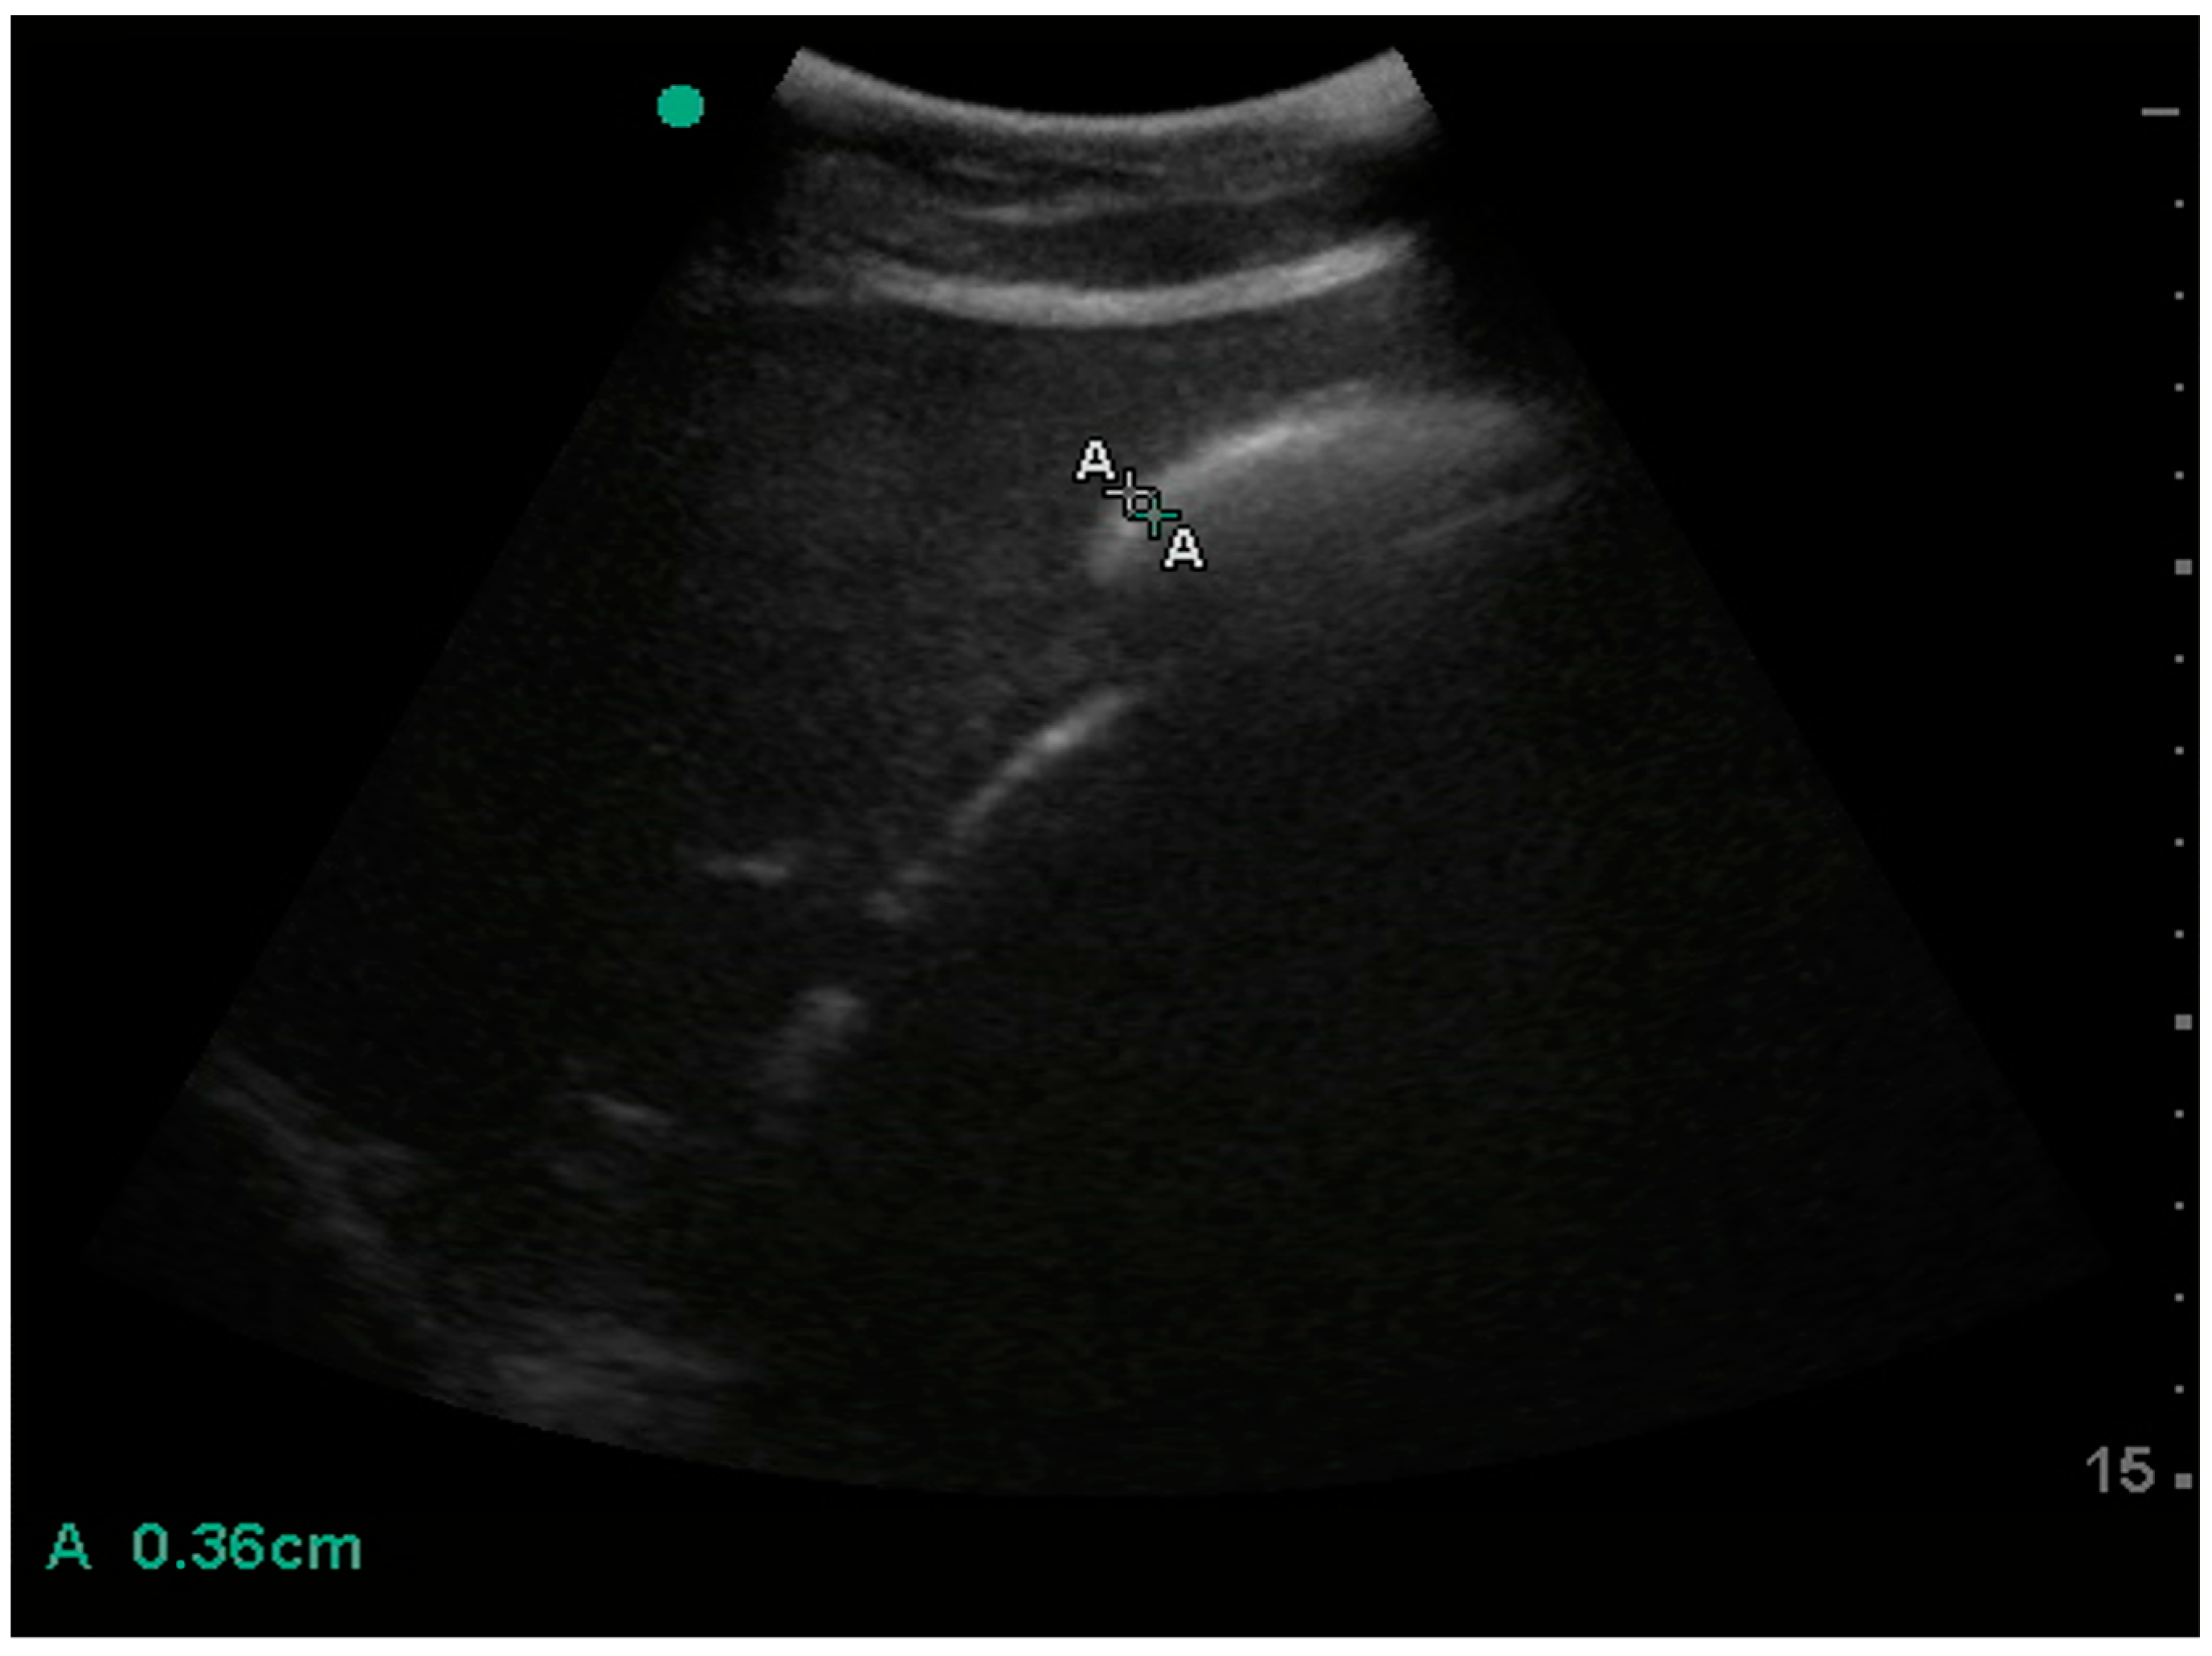

3. Results

| Oesophagus | wall thickness | 3.6 (0.7) | 3.5–4.1 | 2.7 | 3.0 | 4.1 | 4.3 | 2.3 | 4.9 | 2.6 |

| diameter | 18.9 (4.8) | 18.5–23.3 | 11.4 | 14.4 | 22.3 | 23.5 | 10.1 | 24.6 | 14.5 | |